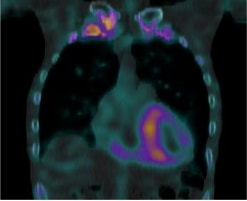

サルコイドーシスは、非乾酪性肉芽腫という病理変化を伴う炎症性疾患です。心臓以外にも眼、皮膚、肺やリンパ節に起こり得ます。心臓においては、心筋の収縮障害から進行すれば心拡大が起きます。不整脈を併発しやすいことも知られています。診断には心臓MRIや血液検査のほかに、心臓にブドウ糖が取り込まれているか調べる核医学検査であるFluorodeoxyglucose-Positron Emission Tomography(FDG-PET)が病勢の把握に有用です。

心サルコイドーシスの活動期

心サルコイドーシスの活動期

ステロイド治療により

ステロイド治療により炎症・免疫反応が軽減